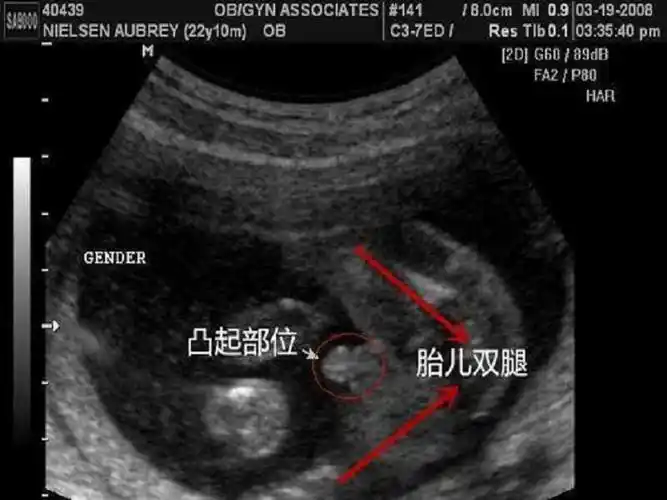

2,男宝宝的屁股位置会微微上翘,后背脊柱成圆弧状,因为要留空间发育